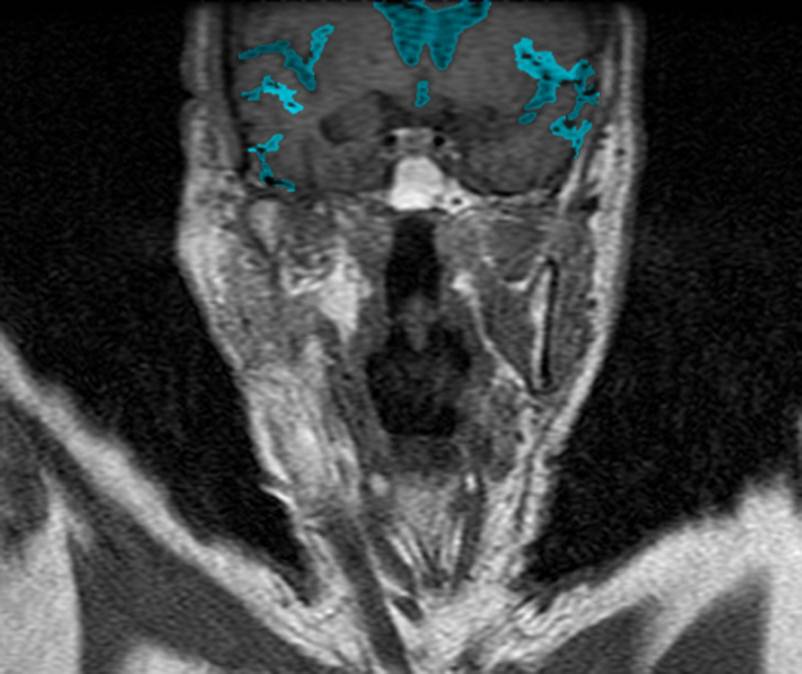

CT: Brain Atrophy

10 Years-Normal Gyri             65 Years-Enlarged Gyri